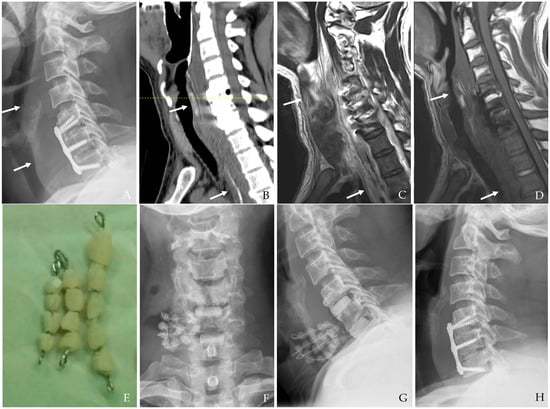

In the case of deep surgical site infections, particularly those involving hardware-related infections, antibiotic-loaded cement beads can be an effective adjunct to systemic antibiotic therapy [16,31,32,33,34]. These beads provide localized, high-concentration antibiotic delivery to the infected site while minimizing systemic toxicity. Their use is particularly beneficial in (a) persistent deep infections resistant to standard antibiotic therapy, (b) cases where hardware preservation is desired, as the beads can help suppress infection without immediate implant removal, and (c) post-debridement infection control, helping prevent bacterial recolonization in the surgical cavity. Common antibiotics used in cement beads include vancomycin, gentamycin, and tobramycin, tailored to the suspected or confirmed pathogens. The beads may be placed temporarily and later removed once infection control is achieved or may serve as a bridge before definitive surgical reconstruction (Figure 8). Newer biodegradable antibiotic carriers are under investigation to improve drug delivery and minimize the need for secondary procedures for removal.

Figure 8. The patient underwent C5-6-7 anterior cervical discectomy and fusion (A). At postoperative 3 days, postoperative infection occurred with retropharyngeal abscess and mediastinal extension (white arrows) (BD). Therefore, the patient underwent the removal of the anterior plate and screws, evacuation of retropharyngeal abscess, irrigation/debridement, and antibiotic-loaded cement beads (EG). The patient underwent C5-6-7 revisional anterior cervical discectomy and fusion 2 weeks after reoperation and achieved a cure for the infection (H).